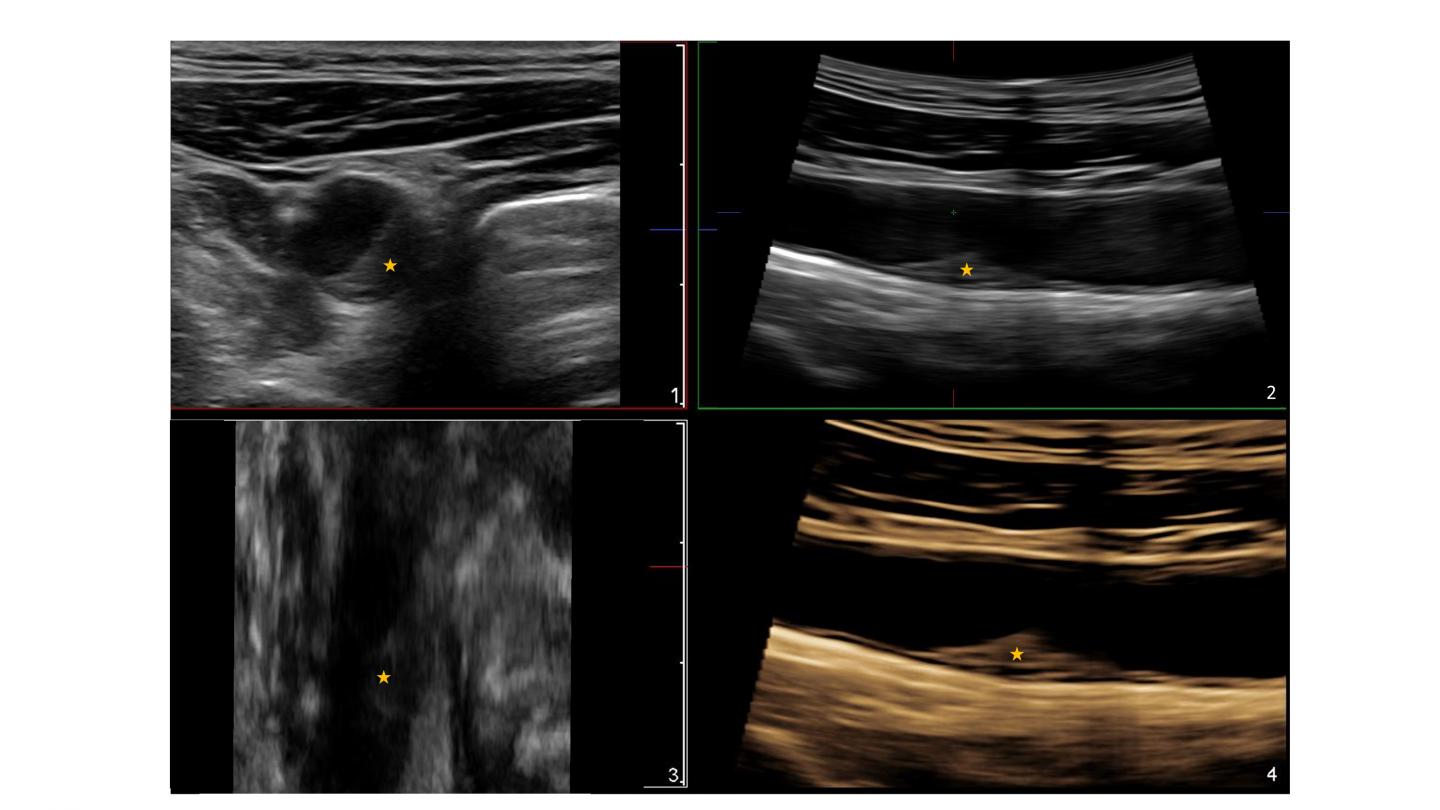

Asterisks indicate the presence of an atherosclerotic plaque in the common carotid artery detected by 3D ultrasound. The plaque does not cause significant obstruction of the artery (<50%). The size and shape of the plaque can be determined in 3D, allowing accurate monitoring of changes in volume over time that indicate progression of the disease.